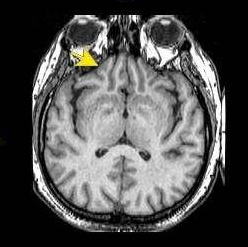

松果体区肿瘤的症状可以随其不同的组织学而不同。出现颅内压升高症状和体征的患者需接受头部CT扫描或MRI检查,以评估紧急处理的必要性。松果体区肿...

松果体区肿瘤的病因 松果体区肿瘤儿童期的发病率是成人的两倍多。肿瘤可导致脑积水和颅内压升高,压迫邻近器官的组织,眼睛不能上视、耳鸣、听力丧...